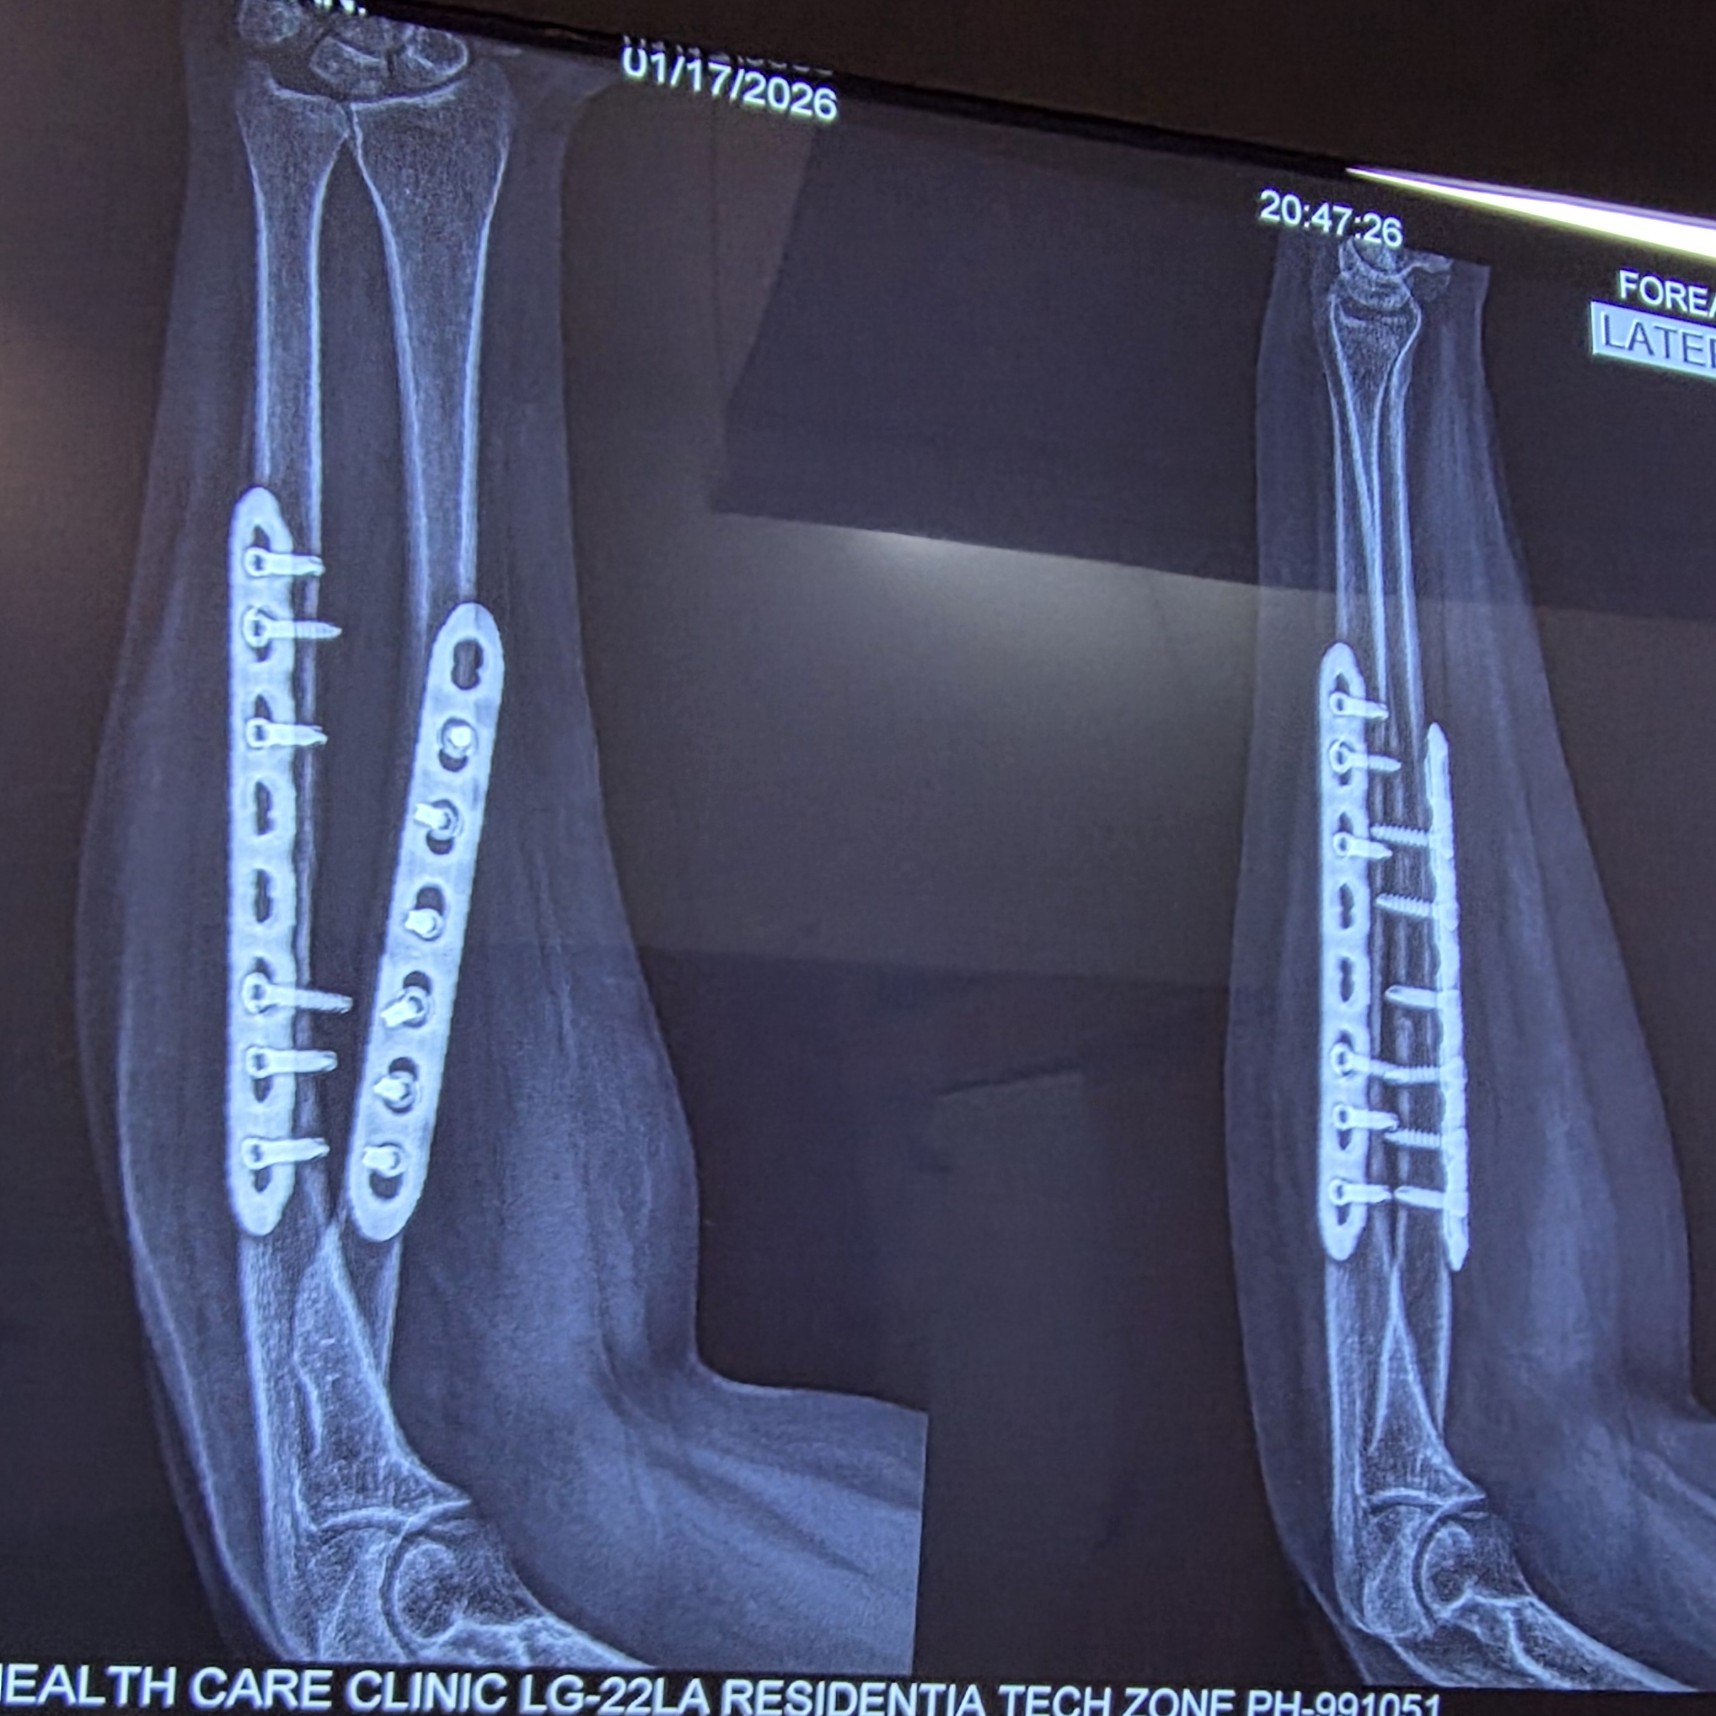

Fractures of forearm bones

treatments